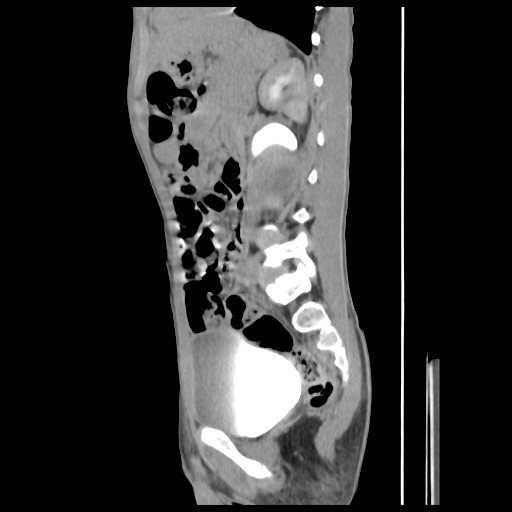

current CT images: